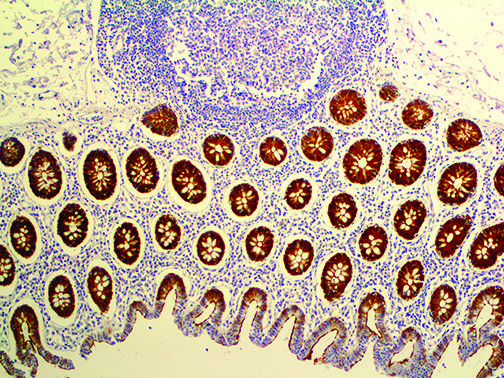

This activation induces inflammatory monocytes to highly express IL-6, starting a localized and then systemic cascade effect that results in hyperproduction of IL-6, which accelerates the inflammatory process. Because IL-6 also increases vascular permeability, excessive levels cause blood vessels to become very leaky. This, along with clotting factors released from vascular endothelial cells, stimulates the coagulation cascade, resulting in microthrombosis (tiny clots), which leads to ischemia and tissue death of the kidney, intestines, heart, liver, brain and extremities.